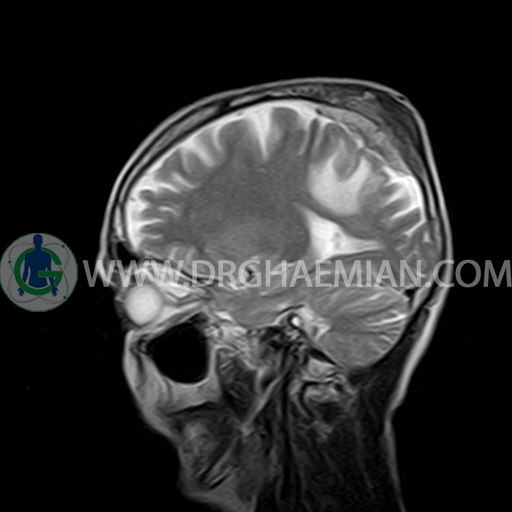

ام آر آی مغز با استفاده آهنربا های قوی و امواج رادیویی تصاویری از مغز و بافت های عصبی پیرامونی آن ایجاد می کند. در این کیس مننژیوم به همراه هیپراستوز استخوانی سمت چپ دیده می شود.

BRAIN MRI

(Without contrast)

Technique:Axial FLAIR, Axial, sagittal, FSE T2, coronal T1 .

a well – defined dural based mass lesion ( 27x55mm ) in left parietal region with signal change in adajacent bone suggestive for meningioma with bone hyperosteosis

mass effect & edema in left parietal lobe

are seen

COMMENT : MRI with contrast is recommended .